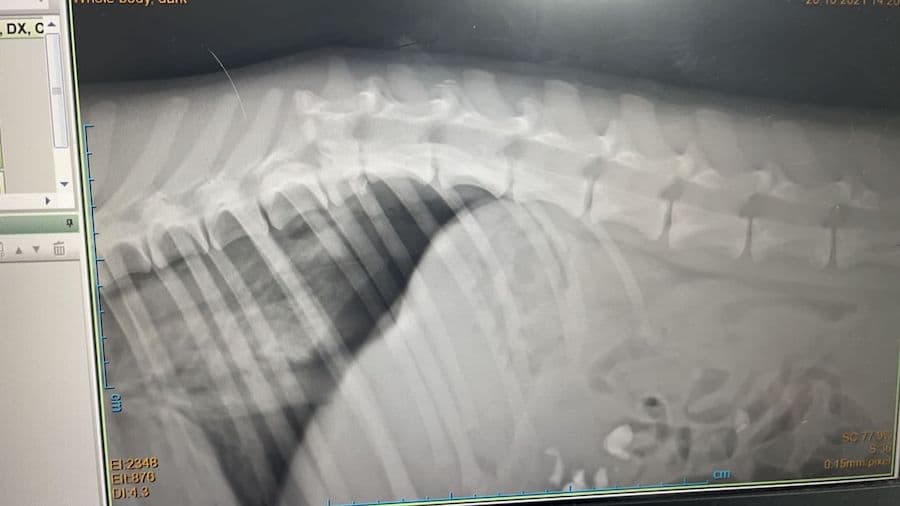

Biscotto (deutsch: Keks) ist etwa zwei Jahre alt und wurde am 20.10.2021 als Streuner am Stadtrand von Tirana in Albanien angefahren gefunden. Ein engagierter Tierschützer brachte ihn in die örtliche Tierklinik, wo er untersucht und geröntgt wurde. Dabei stellte sich heraus, dass seine Wirbelsäule gebrochen und der hinterer Teil seines Körpers gelähmt ist. Glücklicherweise zeigten die Untersuchungen keine Verletzungen der inneren Organe. Mittlerweile – 2 Wochen später – gibt es gute Entwicklungen: Biscotto kann wenn er im Freien ist, selbstständig Urin und Kot absetzen. Seine Hinterbeine zeigen etwas Aktivität. Manchmal schiebt und zieht er sie bei Bewegung zurück und er kann für einige Sekunden auf allen vier Beinen stehen! Er ist ein fröhlicher, freundlicher Hund der Aufmerksamkeit und Pflege braucht, die er in Albanien nicht erhalten kann, zumal es dort keine spezialisierten Einrichtungen für Tiere mit Handicap gibt. Aktuell lebt er in einem Käfig und es wird verzweifelt ein Zuhause oder eine Unterkunft gesucht. Wir leisten Vermittlungshilfe und hoffen so, dass der junge Rüde einen Platz findet. Interessenten melden sich bitte bei: Videos und weitere Fotos gibt es auf der facebook-Seite (in italienischer Sprache) für die Adoptionskampagne von Biscotto: